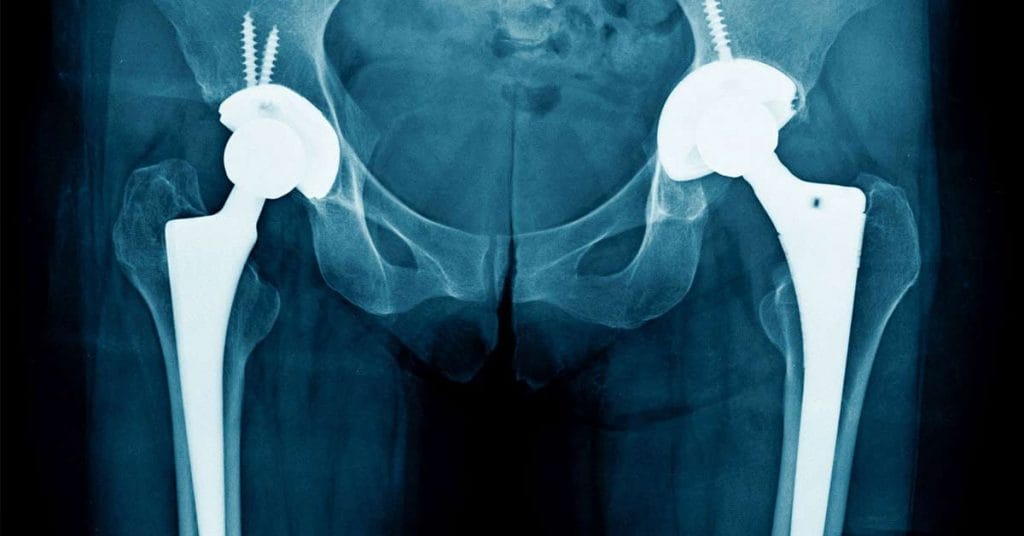

Cada vez es mayor el número de artroplastias realizadas a nivel mundial. De acuerdo con el Hospital Universitario de Bellvitge ubicado en Barcelona, “más de un millón de estas cirugías se han realizado en las últimas décadas”.

Sin embargo, los resultados clínicos pueden verse afectados de manera negativa debido a las infecciones periprotésicas de articulaciones (IPAs), una complicación que, según el Mexican Journal of Orthopedics, tiene una incidencia que varía entre el 0.1% y el 3.0% y cuyo riesgo puede duplicarse en artroplastias de revisión.

Son varios los factores por los que se pueden desarrollar complicaciones periprotésicas, entre ellos la complejidad del procedimiento quirúrgico, así como los propios factores de riesgo asociados al paciente, como diabetes, obesidad o antecedentes de una artroplastia previa en la articulación.